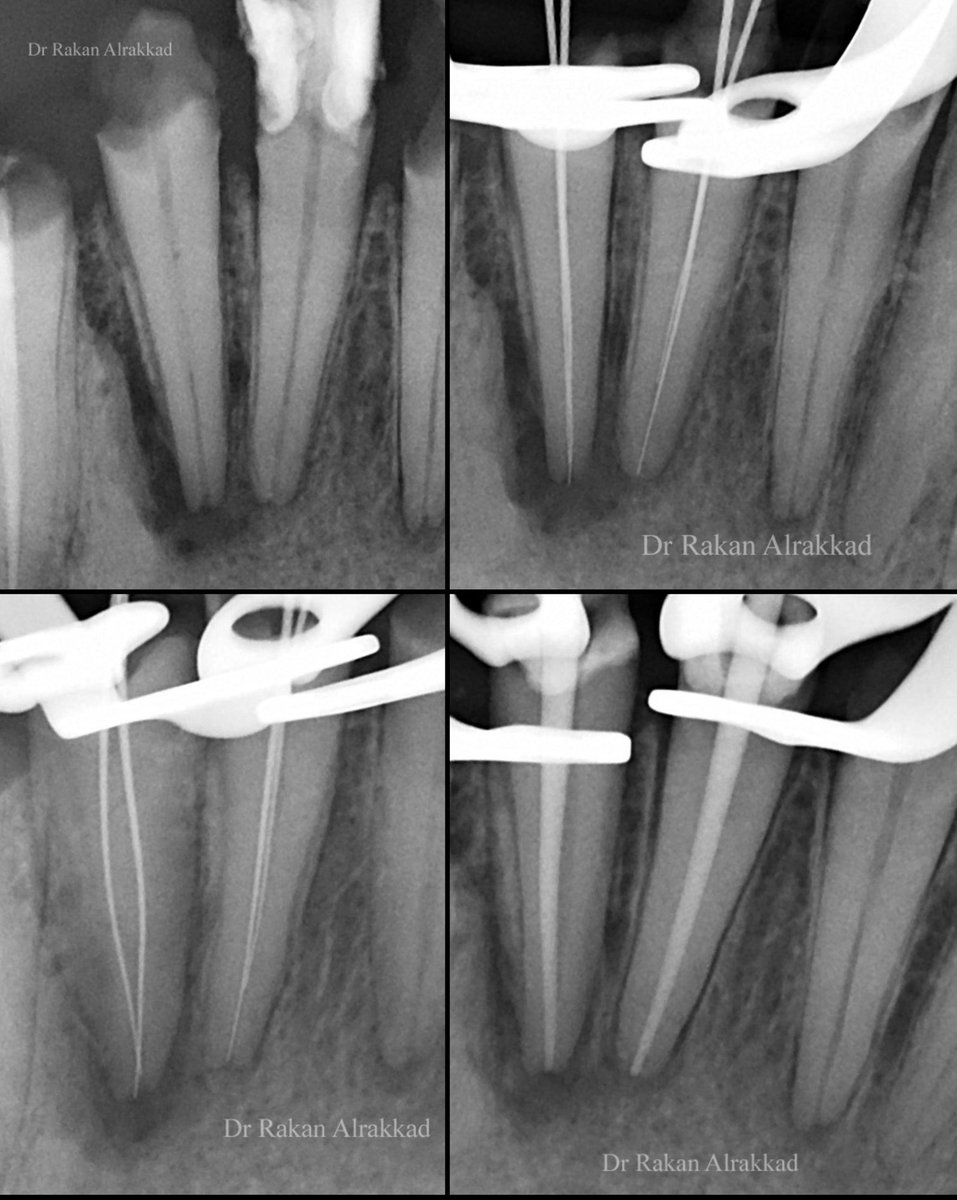

علاج عصب لضرس علوي لطفل تم علاج ٦ قنوات عصبية ولله الفضل وتمت متابعة الحاله لمدة ٦ أشهر و أبشركم بأنه بأتم صحة و عافية MB1, MB2, DB1, DB2, and P with a separate portal of exit. Regarding the P root, what exact condition does it have? *Sorry about the absence of the other PAs.

علاج عصب لضرس علوي لطفل

تم علاج ٦ قنوات عصبية ولله الفضل وتمت متابعة الحاله لمدة ٦ أشهر و أبشركم بأنه بأتم صحة و عافية

MB1, MB2, DB1, DB2, and P with a separate portal of exit.

Regarding the P root, what exact condition does it have?

*Sorry about the absence of the other PAs.